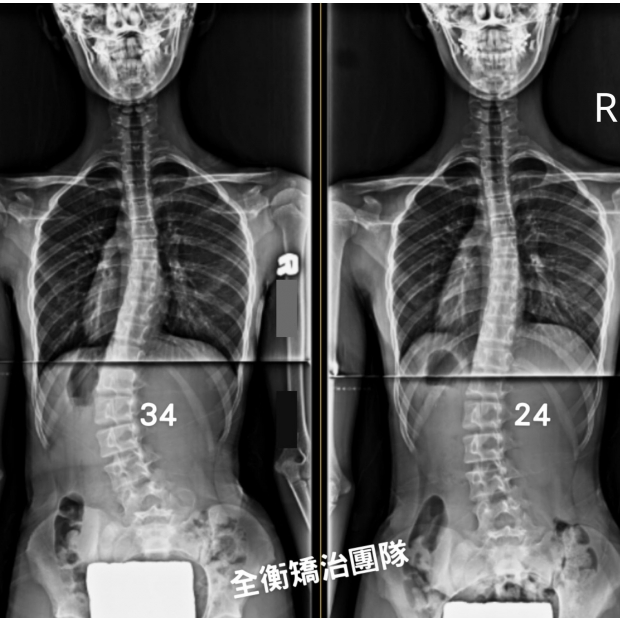

14歲側彎女生努力不懈、持之以恆,追求進步14歲側彎女生努力不懈、持之以恆,追求進步

14歲的女孩,胸腰大彎34°,旋轉15°,骨齡3,柔軟度不佳,

歷經長達兩年多的專業側彎復健運動+穿戴德國施羅斯背架矯治,

體態回正,度數從34°減少至19°,進步44%,旋轉也從15°減少到3° -